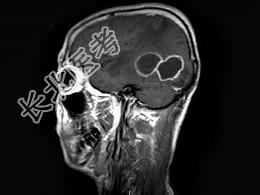

- 单项选择题男,47岁, 发热、头痛、呕吐1周,MRI检查, 最可能的诊断是 ( )

A、脑转移瘤

B、脑脓肿

C、胶质瘤

D、血吸虫性脑病

E、未见异常